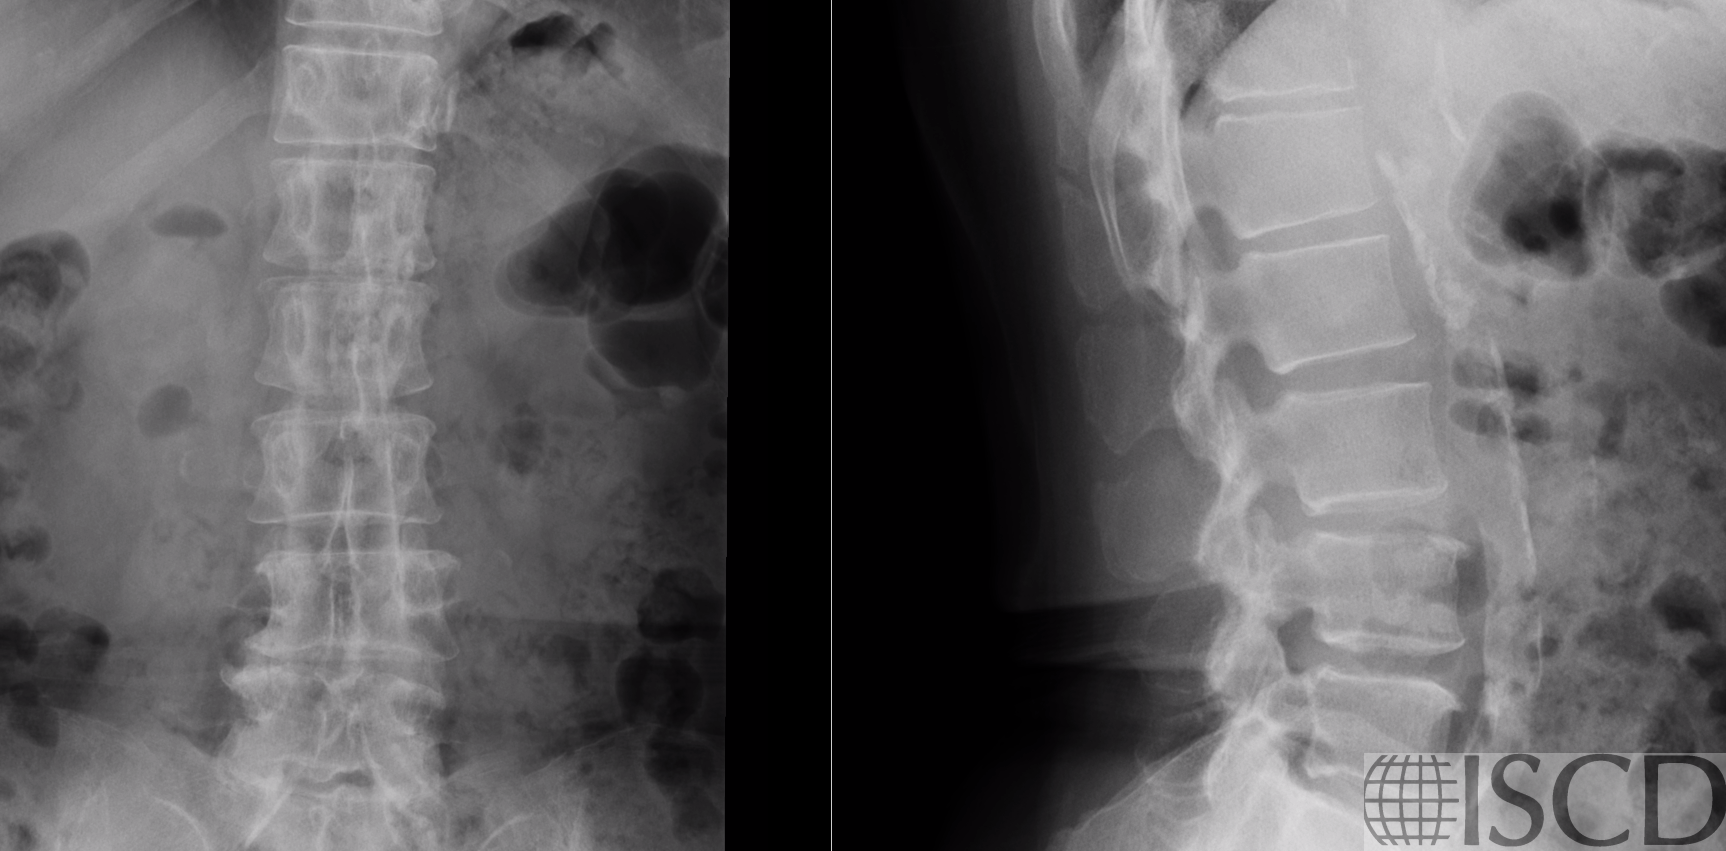

Figure 2 – X-rays of lumbar spine showing dense aortoiliac calcification.

The patient has osteoporosis (minimum T-score -3.0 femur neck). The spine BMD is artifactually elevated by dense aortic calcification that superimposes on the left side of the lumbar spine, see arrow (T-score +0.5). All vertebral levels are affected — there is no saving this spine!